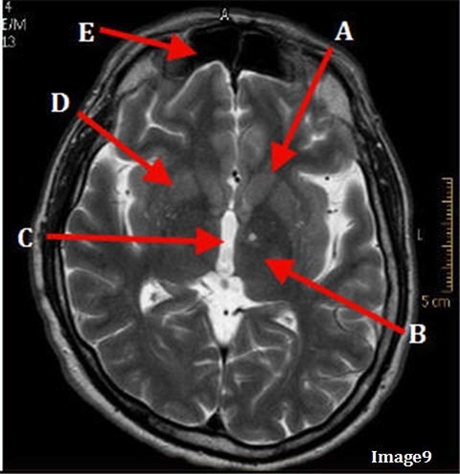

Image weighting and axis

T2 Axial

A

Basal Ganglia

B

Posterior horn lateral ventricle